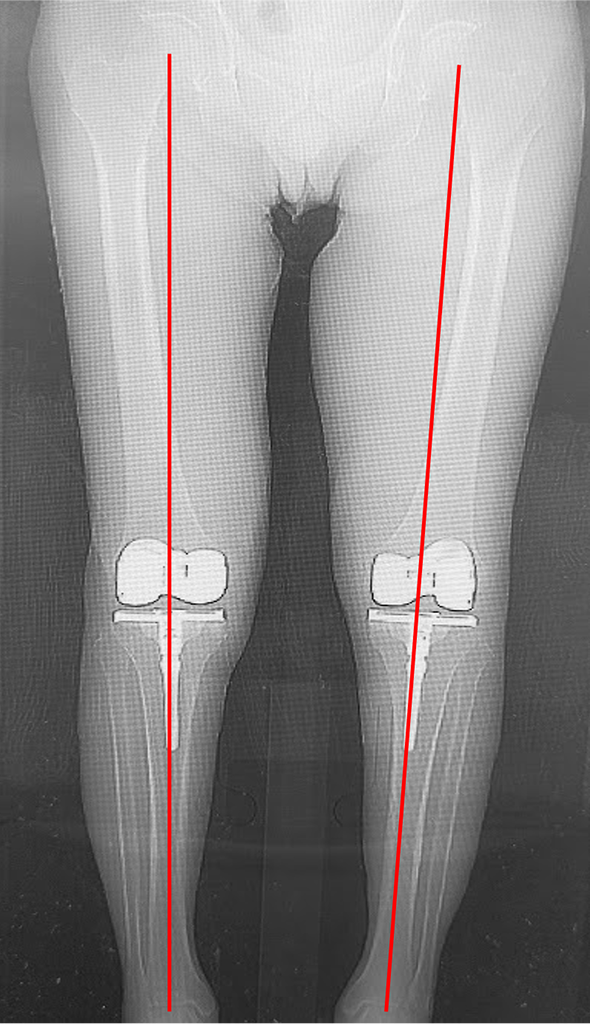

<術後の下肢全長>

術前は高度なO脚を呈していましたが、術後は下肢がまっすぐになり、股関節と足関節の中心を結ぶライン(赤線)がひざ関節の中心を通っています。

当院にて両側の人工ひざ関節全置換術(TKA)を施行。

高度のO脚変形があり、歩行時のひざの不安定感も強い症例です。

キネマティックアライメント法で手術を行いました。

キネマティックアライメントとは、ひざ本来の靭帯のバランス、下肢の形を取り戻すことに重点を置いた方法です。

〈下肢全長の変化〉